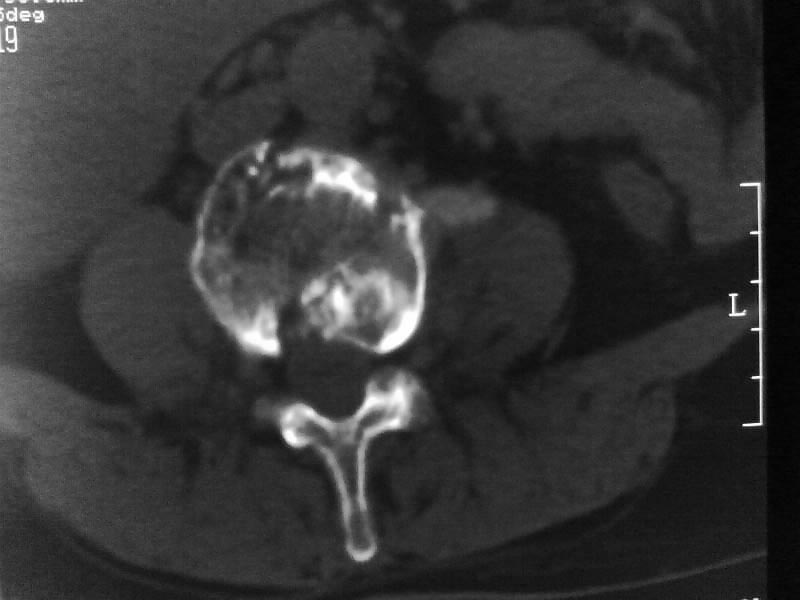

定位相示l2呈楔形改变(ct示陈旧性骨折改变,图像未传),l4.5椎体融合,以下是l4.5ct平扫.请各位看看,

考虑结核(有破坏、硬化及死骨)。

1、三四椎体结核,2、水平骶椎。

1、l1压缩性骨折(陈旧性)。

2、l3、4椎体结核。

就是腰1压缩性骨折,腰3\\4椎体结核(融合),水平骶椎.

支持 l1椎体陈旧性压缩性骨折;l3、4椎体结核(融合);水平骶椎。